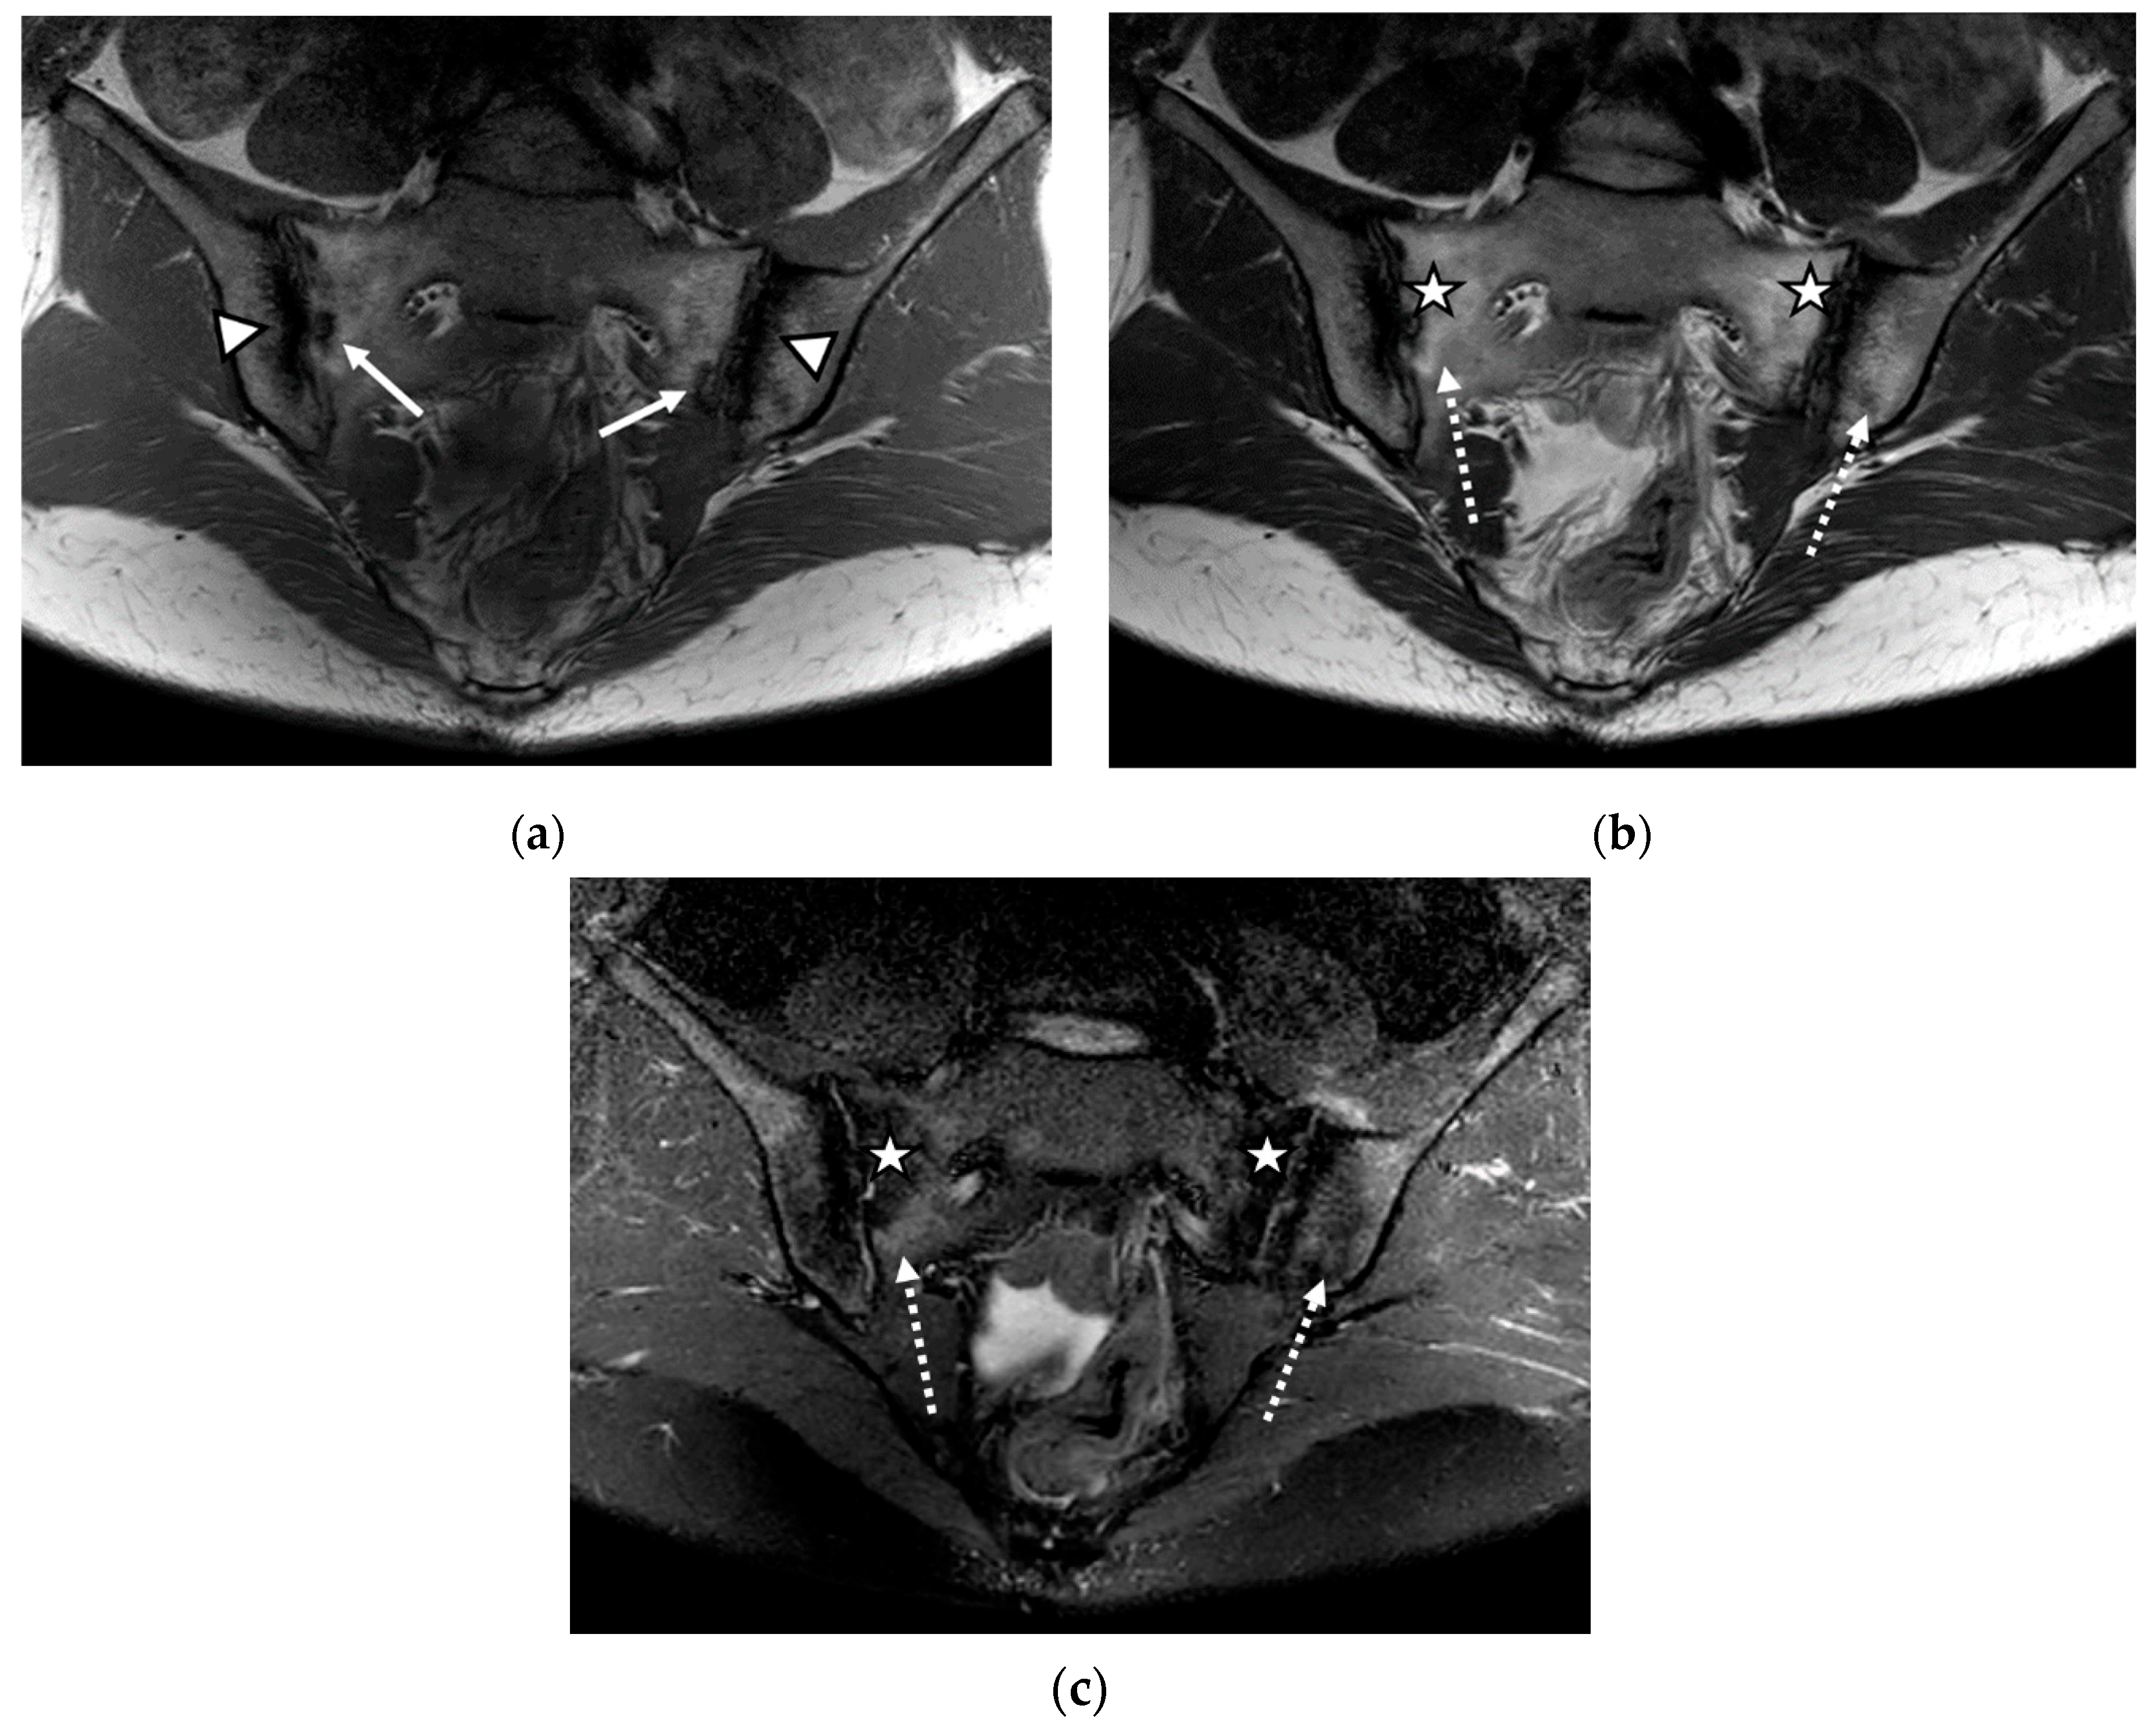

We evaluated 68 sacroiliac joints. The prevalence of MRI-detected abnormalities is presented in Table 2. The results of the SR were considered as the reference data. Inflammatory and structural changes were detected on the MRI sequences of the sacroiliac joints. The most frequently encountered inflammatory change, both on the left and right sacroiliac joint, was the presence of bone marrow edema (44.11–58.82%), followed by enthesitis (17.64–26.47%) and synovitis (11.76–17.64%). Regarding structural changes, the most prominent was subchondral sclerosis (50–59.37%), followed by erosions (35.29–41.17%), joint space narrowing (38.23%), fat metaplasia (17.64–23.25%), and backfill (11.76–20.58%) (Figure 1, Figure 2 and Figure 3).

Figure 3.

The MRI aspect of the sacroiliac joints included pseudo-widening of both sacroiliac joints, with marked bone marrow edema (star) of both the sacrum and the right iliac bone, in the proximity of the ipsilateral sacroiliac joint space, right iliac bone erosions (discontinuous arrow), bilateral subchondral sclerosis (continuous arrow), and fat metaplasia (asterisk), affecting the left iliac bone, and the left part of the sacrum and backfill (arrowhead) of the left sacroiliac joint space: (a) T1-weighted sequence; (b) T2-weighted sequence (without fat suppression); (c) STIR sequence.